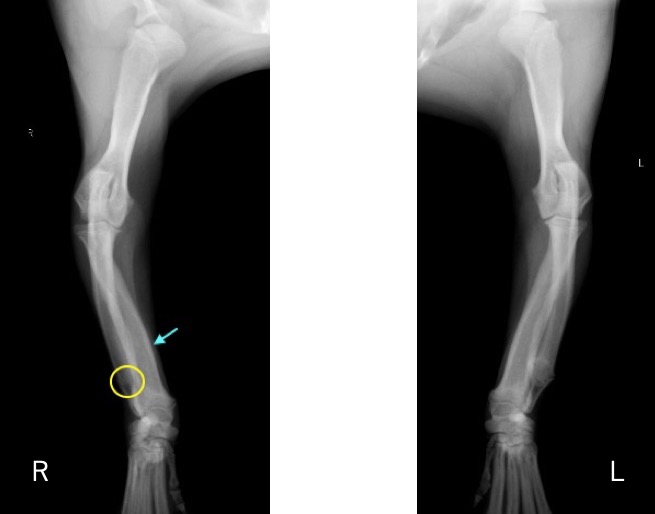

単純X線画像検査において、右側の尺骨遠位成長板領域の不透過性亢進、橈骨の頭側湾曲、鈎状突起と上腕骨顆の間隙が広がっている所見が認められたため、尺骨遠位成長板早期閉鎖が疑われました。

前腕の側面像 (黄丸;尺骨遠位成長板の不透過性亢進 青矢印:橈骨の湾曲 赤矢印:鈎状突起と上腕骨顆の間隙)

前腕の頭尾側像 (黄丸:尺骨遠位成長板の不透過性亢進 青矢印:橈骨の湾曲)